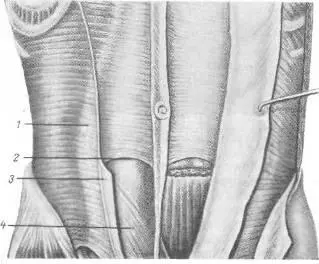

Рис. 36. Хирургическая анатомия полулунной (спигелиевой) линии (по В. II. Воробьеву и Р. Д. Синельникову).

1 — linea serailunaris; 2 — linea semicircularis; 3 — vagina m. recti abdominis ( передний листок ); 4 — fascia transversals.